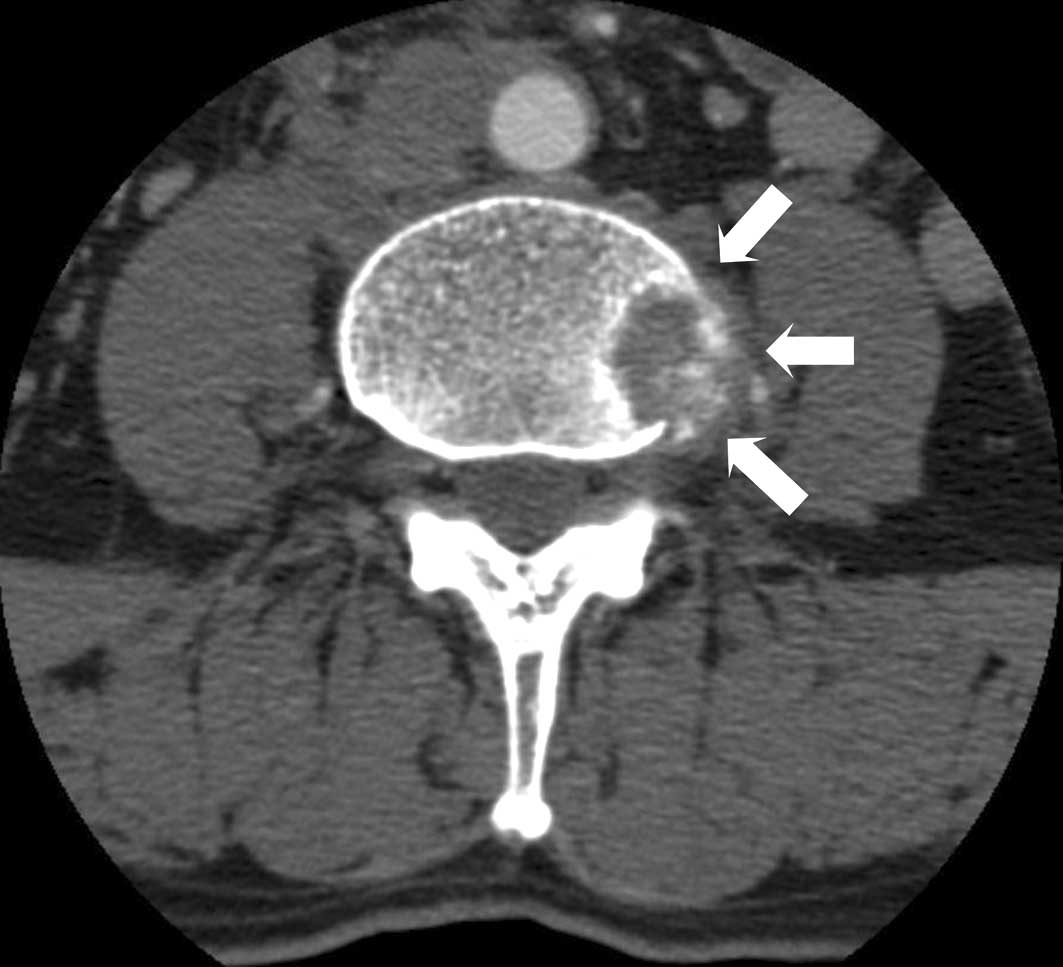

Positron emission tomography showed an increased uptake at the sternum, lumbar vertebrae, rib and retroperitoneal lymph node, with no abnormal uptake in the gastrointestinal tract (Fig. 4). The patient complained of persistent back pain, and a thoracolumbar spinal CT showed an osteolytic lesion extending into the paravertebral area at the 2nd and 4th lumbar vertebral bodies (Fig. 5). Biopsy of the oeteolytic lesion at the 4th lumbar vertebral body revealed metastatic adenocarcinoma upon pathology. A 5-FU- and cisplatin-based combination of chemotherapy and radiotherapy was administered. However, a follow-up bone scan and CT showed that the metastatic lesions had progressed, and the patient succumbed to the disease 15 months later.